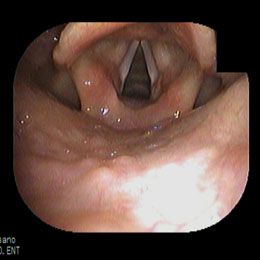

正常な声帯 吸気時

当院における内視鏡診療の中核をなすのがこの電子ファイバースコープです。 鼓膜や鼻の奥、のどの観察は耳鼻咽喉科にとって欠かせないものですが、当院では原則として鼓膜の観察は、この電子ファイバースコープを用いておこなっています。 ファイバーと呼ばれるだけあって、柔らかい素材でできており、細く曲がったところもスルスルと通り抜けて目的の場所をくっきりと映し出してくれます。 耳の中(外耳道)や鼻の中がまっすぐな人はいません。電子ファイバースコープはクネクネ曲がりますので、耳、鼻、のどの観察にもってこいです。当院の電子ファイバースコープは直径2.6mmと世界でも細径クラスです。

電子ファイバースコープを用いることによって「裸眼もより正確な診断ができる」ことと、患者様にも鼓膜の状態をご覧いただけて、その画像を時系列で保存し閲覧ができるため、患部の状態の経過(良くなってきているのか、悪化しているのか?)が一目瞭然でご確認いただけます。